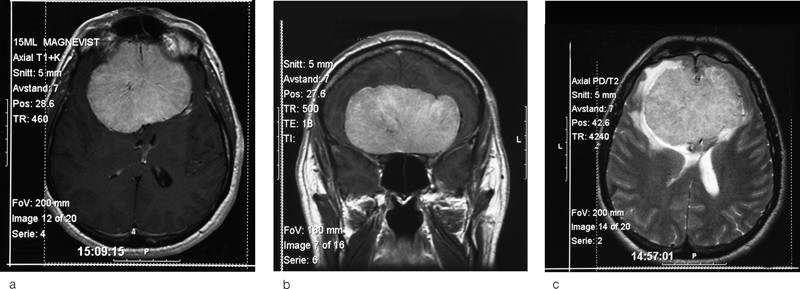

Etter noen måneder på hybel var hans evne til å ta vare på seg selv betydelig redusert. Det var hele tiden kontakt mellom ham og familien, og hans kone kontaktet fastlegen for å melde sin bekymring. Fastlegen hadde også undret seg da pasienten hadde uteblitt og kommet for sent til timer, noe som var utypisk for ham. Pasienten viste selv liten innsikt i egen situasjon. På grunn av insulinavhengig diabetes mellitus gikk han regelmessig til kontroll hos fastlege. Fastlegen valgte å få utført CT av hjernen, og undersøkelsen avslørte en stor kontrastoppladende lesjon basofrontalt. Lesjonen målte 8 x 7 x 5 cm og det var betydelig hevelse i omkringliggende hjernevev. Radiolog antydet at lesjonen kunne være et olfactoriusmeningeom. Allmenntilstanden var svekket. Han ble innlagt i sykehus og raskt overflyttet til nevrokirurgisk avdeling hvor det ble tatt supplerende MR-bilder (fig 1a-c).

Ved innkomst var han våken, men kun delvis orientert for tid, sted og situasjon. Nevrologisk undersøkelse avslørte ingen sikre fokalnevrologiske utfall, men han samarbeidet dårlig ved undersøkelse av hjernenerver og ved oftalmoskopi. Hans symptomer og tegn var forenlige med den påviste intrakraniale svulsten. Det ble gjort ukomplisert bifrontal kraniotomi og ekstirpasjon av svulsten. Histologisvaret bekreftet meningeomdiagnosen.